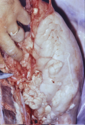

Incisión ganglio l. bronquial

(ganglio inspector): hallazgo de lesión TBC

591x877, 350.0 KB